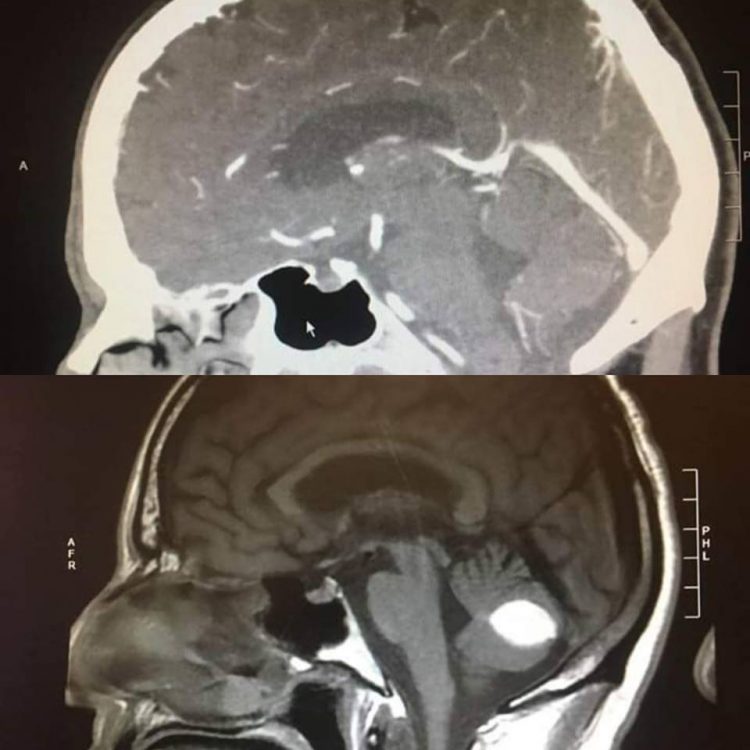

Неожиданное выздоровление мужчины из Калифорнии сбило с толку всех врачей. За день до запланированной операции по удалению предполагаемой опухоли головного мозга, заключительное КТ показало, что масса в его мозгу чудесным образом исчезла.

Пол Вуд, житель городка Лоди, в Калифорнии, начал жаловаться на мучительные головные боли и головокружение несколько месяцев назад и получил несколько серьезных диагнозов от врачей. Нейрохирург в Калифорнийском университете Сан-Франциско сказал ему, что у него кровоизлияние в мозг, в то время как рентгенолог сообщил, что КТ-сканирование показало опухоль. Оба диагноза требовали рискованной операции на головном мозге, но за день до запланированного хирургического вмешательства заключительная компьютерная томография не обнаружила признаков чего-либо необычного в его мозгу. Врачи до сих пор не могут объяснить что произошло, но Вуд убежден, что это не что иное, как чудо Господне.

Врачи не оспаривают теорию Вуда, поскольку сами не могут логически объяснить что произошло с четким белым пятном, обнаруженном при первоначальном сканировании мозга. Сообщается, что они попросили Пола принять участие в дальнейших исследованиях, чтобы больше узнать о том, что произошло.